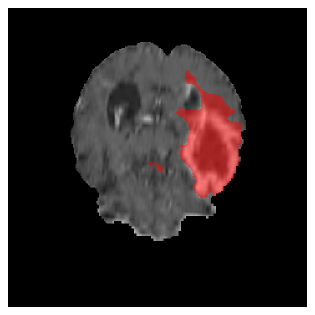

Appendix A Qualitative results

Figure 5 illustrates the segmentation evolution for the same BRATS patient in S2 sequence. The key difference here is that the best buffer-free strategy is EWC (=1), and training on BRATS data starts from episode 2 instead of episode 1 as BRATS is encountered at episode 2 in S2. The cumulative approach retains segmentation across episodes but continues to generate false positives, which become even more pronounced in the final episode. The naive approach, lacking a CL mechanisms, completely overrides previous knowledge, leading to failed segmentation in later episodes. EWC (=1) approach initially maintains segmentation but experiences a sharp decline in episode 4, where it fails to segment the tumor. In the final episode, it undersegments the lesion, missing a significant portion of the tumor. In contrast, the proposed approach consistently preserves segmentation across episodes. While initially introducing false positives, it gradually refines predictions, retaining the tumor region while minimizing misclassifications. It maintains clear tumor delineation by the final episode, demonstrating effective knowledge retention and adaptability throughout training.